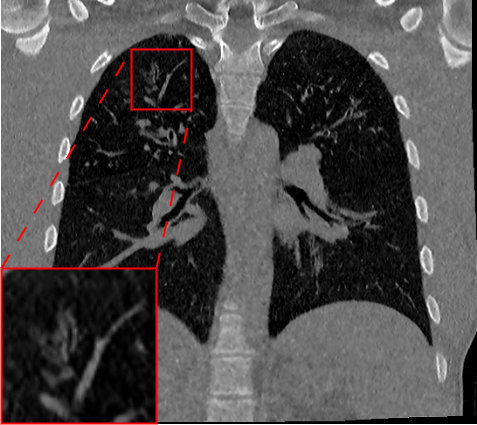

Fig. 2 presents a visual comparison of lung coronal sections from different models. The model using L1 loss results in blurred images, with particularly poor bone reconstruction. In contrast, the MedicalNet-based model produces sharper images but introduces artifacts in anatomical areas. Models based on AFP loss offer visually appealing results, with well-reconstructed anatomical bones and lung tissue. Additionally, only NaviAirway and HAL methods provide detailed bronchial reconstruction, as highlighted in the zoomed-in section.

Table 1 presents a quantitative evaluation of the model’s performance on lung MR to CT synthesis, based on the MAE, SSIM, Dice score, and NSD between synthesized and ground truth CT images. The adapted nnU-Net trained with L1 loss delivers the best performance on intensity-based metrics, yielding a MAE of 48.72 and an SSIM of 0.837. In contrast, other models based on perceptual loss or AFP loss achieve average MAE results but maintain competitive SSIM values, for example, the AFP loss with TotalSegmentator embeddings achieves an SSIM of 0.828. In the context of airway segmentations using the NaviAirway pipeline, the adapted nnU-Net models with AFP loss from NaviAirway and HAL’s embeddings deliver the best performance, achieving the highest Dice score of 0.584 and NSD value of 0.723. Conversely, models employing L1, perceptual, or AFP loss with TotalSegmentator’s embeddings yield poorer results, lacking precise bronchial reconstruction. The GAN-based SPADE method generally underperforms compared to nnU-Net, but adding AFP loss to SPADE enhances its performance. These metrics align with qualitative analysis from Fig. 2 and Fig. 3, with the models using AFP loss delivering the best performance in airway reconstruction.

![]() |

| Real CT | L1 | Perceptual | AFP TotalSeg | AFP Navi | AFP Navi + HAL |

Table 2 and Fig. 4 provide a comparative evaluation of the models on airway lesions segmentations using the Holistic Airway Lesions (HAL) pipeline with Dice score and NSD. Models leveraging the AFP loss using HAL’s embeddings provide the best performances. Specifically, for bronchiectasis, the model using HAL’s embeddings achieves an NSD of 0.516, significantly outperforming the L1 loss model which only reaches 0.373. Additionally, the model with AFP loss using only NaviAirway’s embeddings also shows strong results, while other models are generally of poor quality on this task.